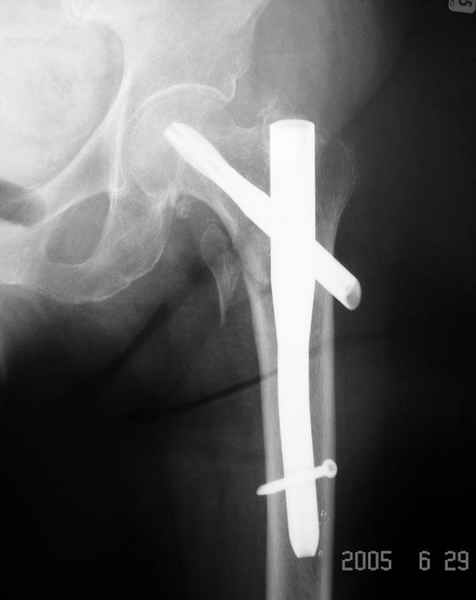

Как раз недавно у меня был примерный случай: больному 36 лет, поступил ночью, травма в результате мотоциклетной аварии, кроме чрезвертельного и спирального перелома левого бедра имеется переломы костей предплечья с этой же стороны. Скелетное вытяжение, а на следующий день больной про оперирован на ортопедическом столе с дистракцией. Чтобы не расколоть чрезвертельный перелом провели временную спицу ближе к переднему кортексу, из малого разреза костодержатель для репозиции, а фиксацию провели антиградным штифтом. Этапы операции на снимках.

Да, сейчас это и у нас самый напрашивающийся выбор. Сделали гвоздем ChM, картинки в приложении.

У молодых реконструкционный гвоздь самое то. При остеопорозе надо что-то помассивнее.